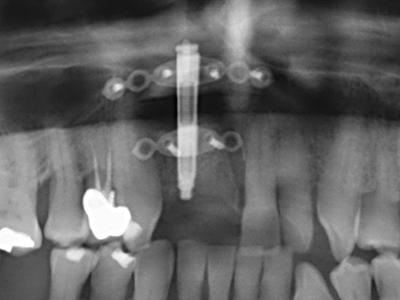

Knochengewebe ist nicht nur rein mineralisch, sondern auch in wesentlichen Anteilen aus Kollagenfasern aufgebaut. Dies gewährleistet neben einer guten Druckfestigkeit eine gewisse Flexibilität, welche für die Durchführung von Augmentationen genutzt werden kann. Bei der klassischen Expansionsplastik im Sinne eines Bone Splittings wird der atrophierte Kieferkamm in seiner Längsachse gespalten und nach Erreichen einer ausreichenden Osteotomietiefe vorsichtig aufgedehnt (Abb. 13-16), idealerweise ohne den Kiefer wesentlich zu deperiostieren (Brugnami, Caiazzo et al. 2014, Stricker, Fleiner et al. 2014). Bewährt haben sich Schrauben- und Plattensysteme mit zunehmender Expansionsdistanz, um die beiden Knochenlamellen unterhalb der Bruchschwelle voneinander zu distanzieren. In der Regel werden Restknochenbreiten von mindestens 3-4 mm gefordert (Chiapasco, Zaniboni et al. 2006), um eine ausreichende Flexibilität und knöcherne Bedeckung der einzubringenden Implantate zu gewährleisten. Ggf. kann eine ein- oder beidseitige vertikale Entlastungsosteotomie die Flexibilität verbessern. Als Alternative zur klassischen Technik wurde eine Kombination mit weiteren augmentativen Techniken vor allem auf der bukkalen Seite beschrieben.

Mittels Piezosägen erfolgt die Anlage des Splittings besonders schonend und ohne wesentliche Dimensionsverluste, so dass sich keine signifikanten Unterschiede von Implantaten im gesplitteten Kiefer im Vergleich zum nicht defizitären Alveolarkamm gezeigt haben (Chiapasco, Zaniboni et al. 2006, Danza, Guidi et al. 2009). Gerade beim lokal begrenzten und tiefen Splitting ist jedoch stets auf eine ausreichende Wasserkühlung zu achten, um thermische Belastungen in den apikalen Osteotomiebereichen zu vermeiden.